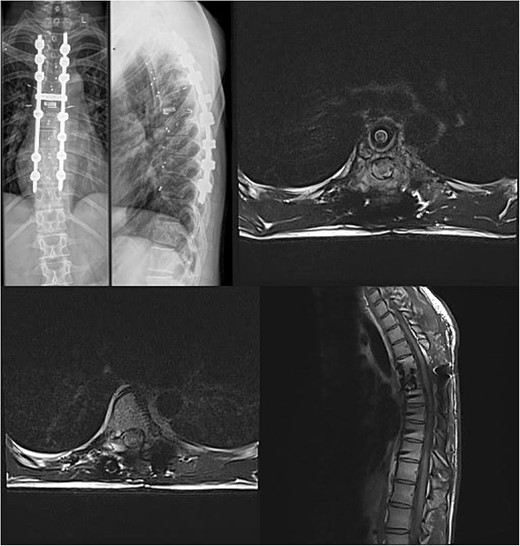

We decided to perform a revision total en bloc spondylectomy at Th6, along with resection of the Th8 pedicle and costovertebral joint, with a partial resection of the adjacent rib. Posterior spinal fixation from Th3 to Th10 was performed using radiolucent carbon screws, and the Th6 body was reconstructed using a radiolucent expandable cage (Figs 3 and 4). During the surgery, MEPs and SEPs were lost, with the patient waking up paraplegic (ASIA score B, VAS pain score 5). Immediate postoperative MRI showed no residual signs of thoracic spinal cord compression due to tumour or haemathoma (Fig. 5). The patient’s neurological status substantially improved the day after surgery, and thereafter, gradually improving over the next few days, allowing the patient to walk independently within 10 days (ASIA score D, VAS pain score 3). A multidisciplinary council decided against postoperative radiotherapy to avoid aggravating neurological symptoms by possibly causing additional damage to the myelopathic spinal cord. On the 11th postoperative day, the patient reported dyspnoea, and urgent CT angiography revealed peripheral pulmonary embolism, which was managed utilizing Deltaparine. Subsequent postoperative course was uneventful, leading to his discharge on the 15th postoperative day, ambulating independently using a walker. MRI follow-up was conducted 6 months postsurgery, followed by yearly checks. At the last follow-up, 2.5 years after the second surgery, there were no signs of tumour recurrence, and the patient exhibited no gait disturbance, back pain, or radiological signs of spinal instability (Fig. 6) (ASIA score E, VAS pain score 0).

Final follow-up X-Ray scan and MRI imaging showing no radiological signs of spinal instability or myelopathy.